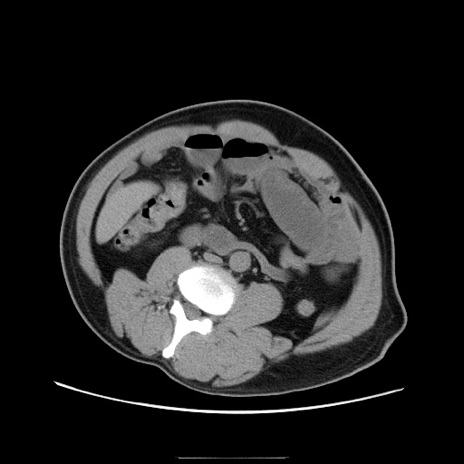

症例22(横断像)

【症例】50歳代男性

【主訴】腹痛

【現病歴】AVMからの被殻出血のため回復期リハ病棟入院中。 本日午後3時頃急に下腹部痛が出現した。

【既往歴】AVM、被殻出血、虫垂炎、高血圧

【身体所見】意識晴明、左半身不全麻痺、会話の理解は良好、36.5°C、腹部:膨隆、全体に板状硬、下腹部正中に圧痛点あり、反跳痛-、筋性防御不明、右下腹部にope scar

【データ】WBC 9400、CRP 0.06